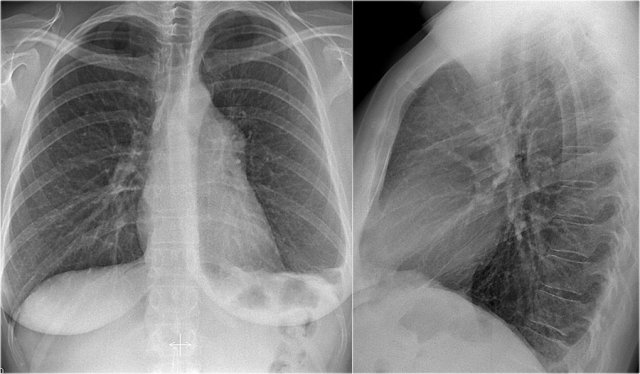

Old films

It is extremely important to always compare with old films, as we will demonstrate in this case.

Actually someone said that the most important radiograph is the old film, since it gives you so much information.

For instance a lung mass, which hasn't changed in many years is not a lung cancer.

First study the chest films.

Based on these films, you could make the diagnosis of congestive heart failure, but the findings are subtle.

Continue with the old film...

Scroll back and forth to the old film.

Once you compare the chest film to the old one, things become more obvious and you will be much more confident in your diagnosis of congestive heart failure:

- The size of the heart is slightly increased compared to the old film, but was already large on the old film.

- The pulmonary vessels are slightly increased in diameter indicating increased pulmonary pressure.

- There are maybe some subtle interstitial markings as a result of interstitial edema.

- There is pleural fluid bilaterally. Notice that the infero-posterior border of the lower lobes has changed in position.